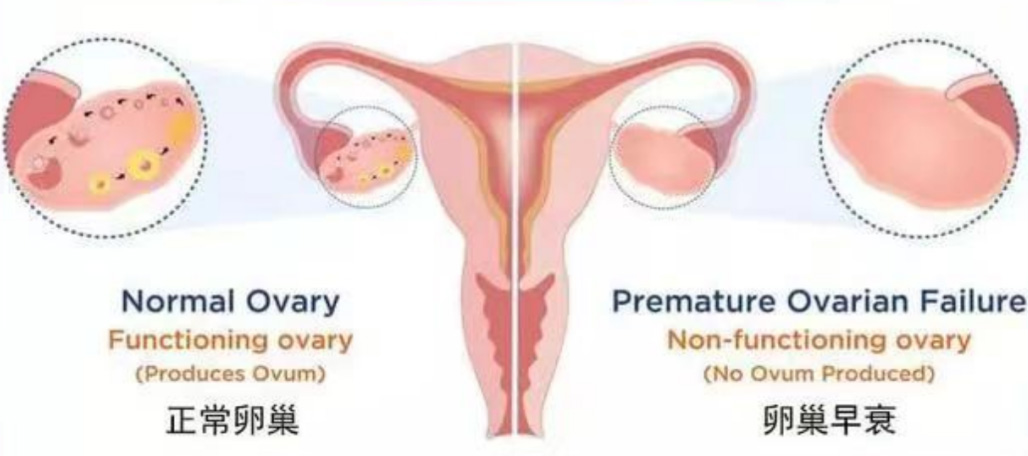

在女性与衰老这场拉锯战中,起着决定性作用的便是卵巢,它就如同花朵的根部,源源不断地输送保持年轻态的重要养料“雌激素”。其主要功能:一是产生并排出卵子,为孕育生命做准备;二是分泌雌激素,以维持女性第二性